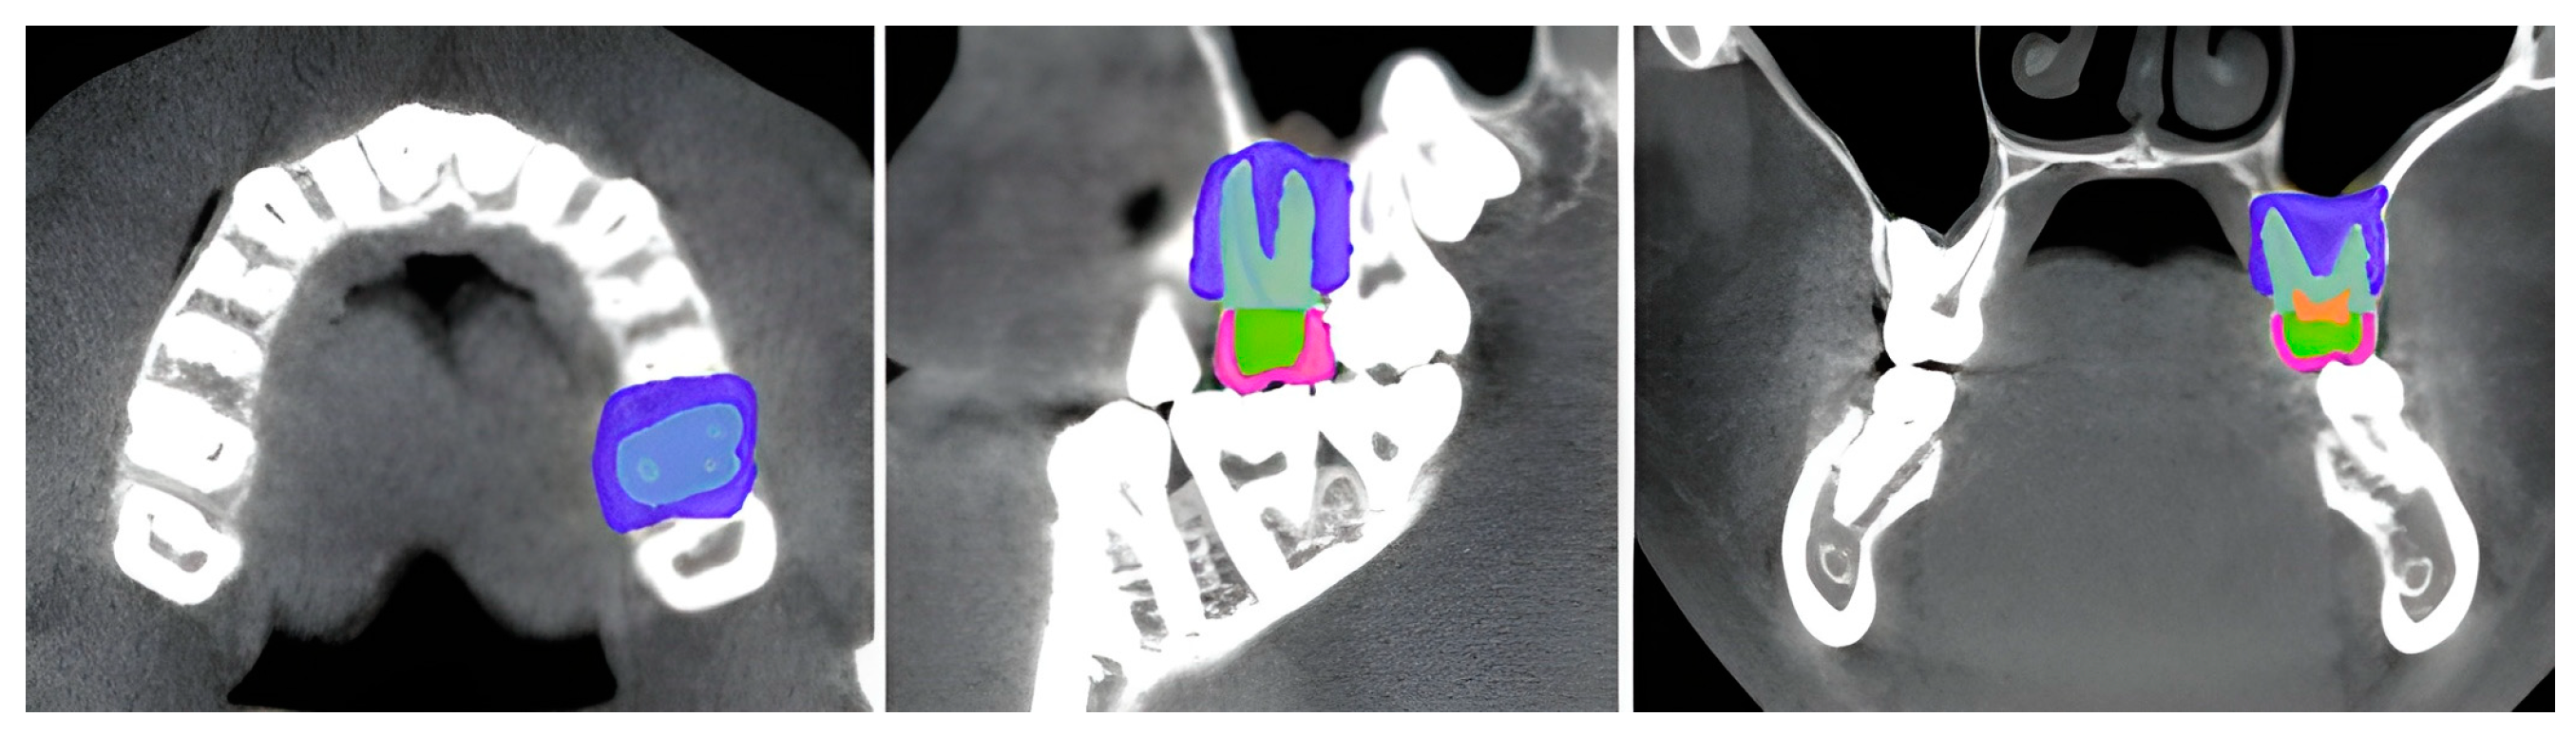

2.2.1. Model Preparation

- Kikinis, R.; Pieper, S.; Vosburgh, K. 3D Slicer: A Platform for Subject-Specific Image Analysis, Visualization, and Clinical Support. In Intraoperative Imaging and Image-Guided Therapy; Jolesz, F.A., Ed.; Springer: New York, NY, USA, 2014; pp. 277–289. [Google Scholar]

- 3D Slicer Community 3D Slicer Sample Data: PreDentalSurgery.gipl.gz, [Online Resource]. 2024. Available online: https://github.com/Slicer/SlicerTestingData/releases/download/SHA256/4cdc3dc35519bb57daeef4e5df89c00849750e778809e94971d3876f95cc7bbd (accessed on 21 March 2025).

- Liao, C.-W.; Fuh, L.-J.; Shen, Y.-W.; Huang, H.-L.; Kuo, C.-W.; Tsai, M.-T.; Hsu, J.-T. Self-Assembled Micro-Computed Tomography for Dental Education. PLoS ONE 2018, 13, e0209698. [Google Scholar] [CrossRef]

- Dot, G.; Chaurasia, A.; Dubois, G.; Savoldelli, C.; Haghighat, S.; Azimian, S.; Taramsari, A.R.; Sivaramakrishnan, G.; Issa, J.; Dubey, A.; et al. DentalSegmentator: Robust Open Source Deep Learning-Based CT and CBCT Image Segmentation. J. Dent. 2024, 147, 105130. [Google Scholar] [CrossRef]